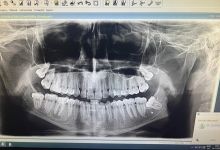

– control radiologic.